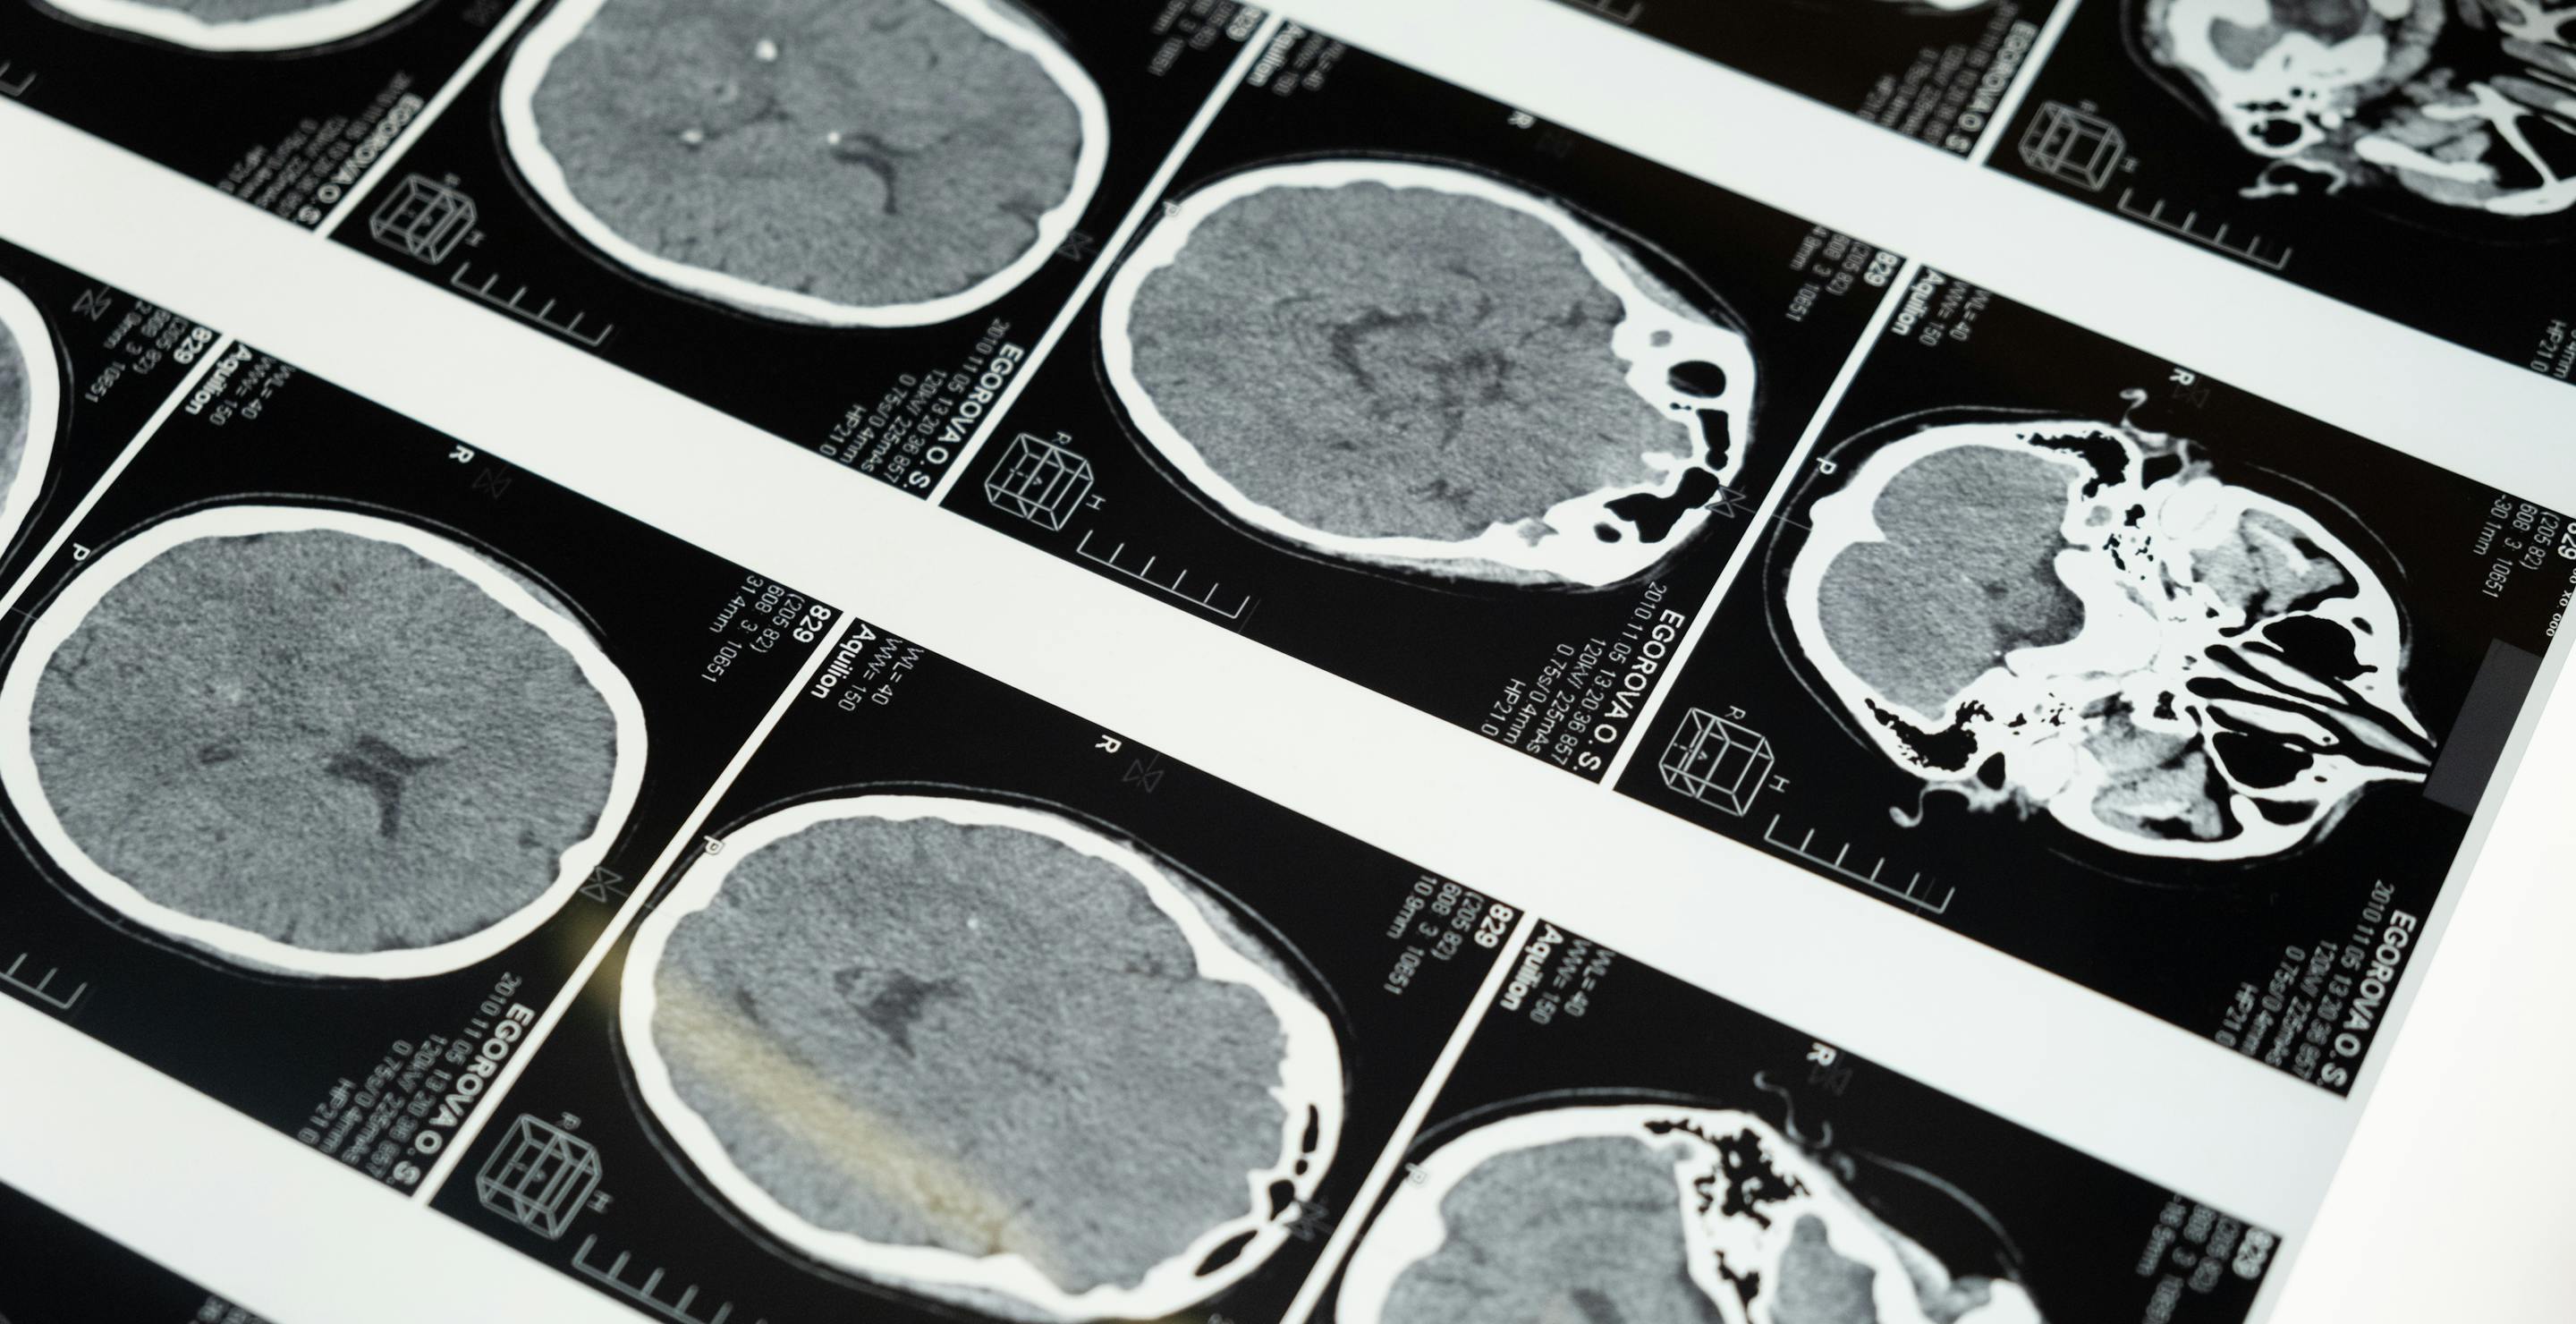

The parasite infects neurons in the brain and prevents them from producing as many extracellular vesicles. These are key in exchanging information, and so when affected, they can cause various issues in cognitive function.

The parasite can lie dormant in the brain for years and reactivate when the immune system becomes weakened or compromised. The effects can be serious, ranging from seizures to neural damage and altered brain connectivity.

The parasite prevents natural regulation in the brain. When the neurons are infected, regulation breaks down, resulting in much higher levels of glutamate. It’s the excess of this that will cause problems.